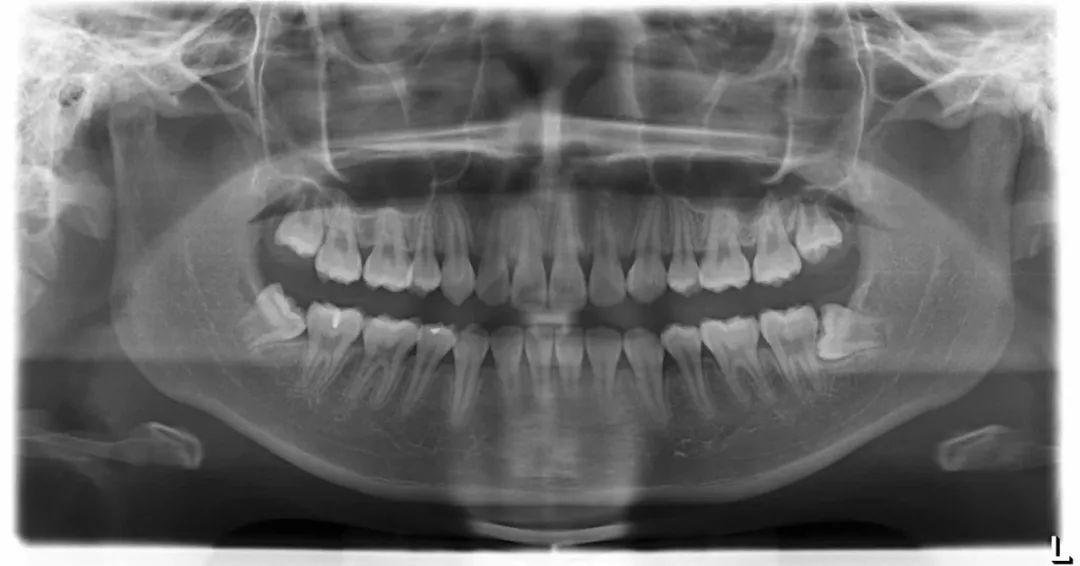

看不见的不等于不存在,也有可能是埋伏了。看牙片就能清晰看到有没有智齿,智齿长的位置怎么样,要不要拔,一切清晰明了。